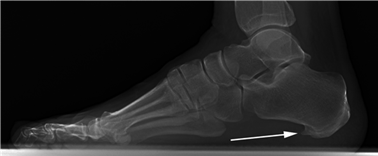

Weight-bearing anteroposterior (AP), lateral, and sesamoid axial radiographs are mandatory. On the AP view, the surgeon measures the Hallux Valgus Angle (HVA, normal < 15°), the Intermetatarsal Angle (IMA, normal < 9°), and the Distal Metatarsal Articular Angle (DMAA). The lateral view is scrutinized for Meary's angle (talo-first metatarsal angle) to identify midfoot collapse, as well as the presence of dorsal osteophytes indicative of hallux rigidus. The sesamoid axial view is critical for assessing the degree of sesamoid subluxation and the integrity of the crista.

Conversely, hallux rigidus represents a degenerative cascade characterized by osteophyte formation, dorsal impingement, and progressive loss of sagittal plane motion at the first MTP joint. While trauma and inflammatory arthropathies can precipitate this condition, the most common etiology is idiopathic, often linked to an elevated or elongated first metatarsal (metatarsus primus elevatus), which alters the joint's instant center of rotation and accelerates articular wear. Recognizing these distinct pathophysiological pathways is paramount for the orthopedic surgeon, as it dictates the selection of joint-sparing osteotomies versus joint-sacrificing arthrodesis.